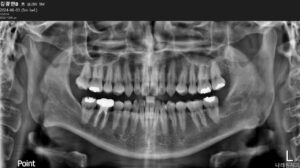

깔끔하게 발치가 마무리된

파노라마 사진입니다.

환자분께서는 발치 후

3일 정도 욱신거리는 통증이 있었지만,

약 일주일이 지나면서

불편감이 거의 사라졌다고

말씀해 주셨습니다.

전 > 후